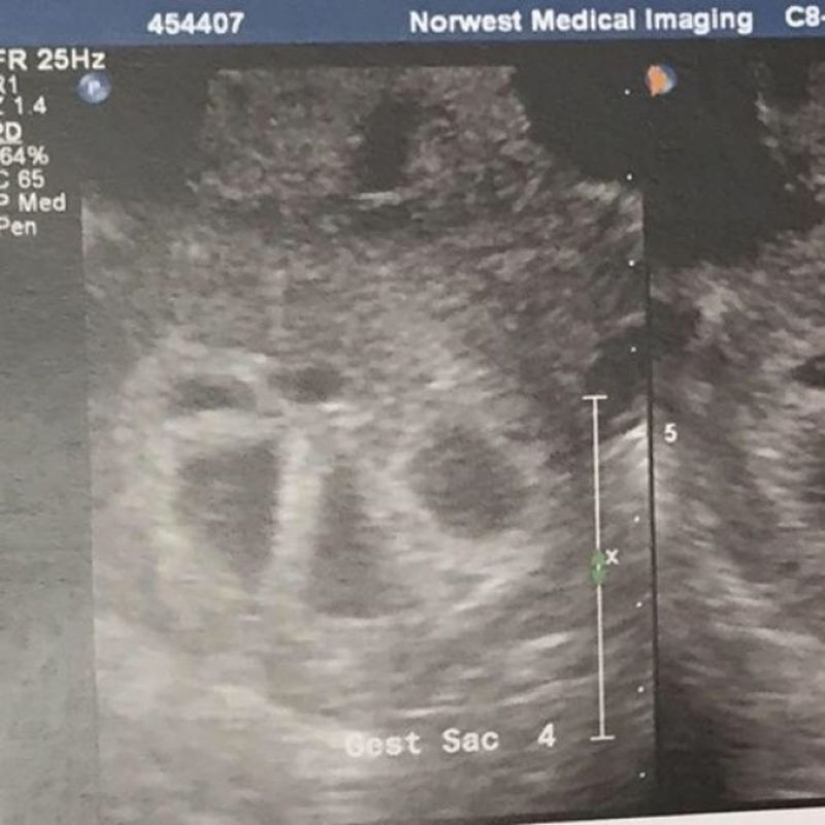

2. "During the first ultrasound, the doctor began to count the fetal eggs: "The first, second, third, fourth, fifth!"", says Kimberly. "Did I hear right? There are FIVE of them??? I asked. And then I lost the power of speech and could only laugh." (By the way, the probability of conceiving quintuplets naturally is 1 in 55 million).